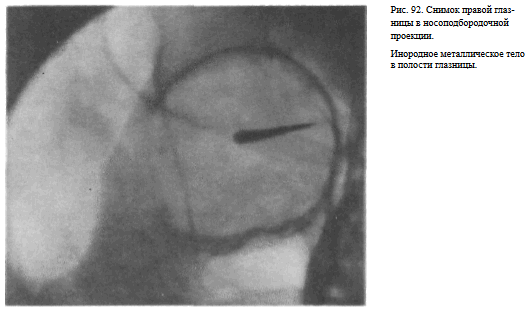

На прицельном снимке каждой из глазниц в этой же проекции, как правило, небольшие изменения структуры стенок, а также мелкие инородные тела глаза видны лучше. Такие снимки широко используют в офтальмологической практике (рис. 92).

Назначение снимка — изучение контуров костей, образующих вход в глазницу, структуры верхней и наружной ее стенок, ширины и контуров верхних глазничных щелей, а также выявление инородных тел в полости глазницы.

В качестве примера информативности снимка глазниц в носолобной проекции для выявления инородных тел глаза и деструктивных изменений стенок приводим два наблюдения.

Одно из них — случай ранения глаза металлической стружкой (рис. 93), другое — случай деструкции верхненаружного края глазницы при доброкачественной опухоли слезной железы (рис. 94).

РЕНТГЕНОЛОГИЧЕСКОЕ ИССЛЕДОВАНИЕ ГЛАЗА СНИМКИ ГЛАЗА С ПРОТЕЗОМ КОМЬЕРГА- -БАЛТИНА

Назначение снимков — локализация инородных тел в глазу и полости глазницы.

Методика выполнения рентгенограмм глазницы с протезом Комбурга — Балтина. Осуществляют анестезию глаза больного путем закапывания в конъюнктивальный мешок 2% раствора дикаина. Протез Комберга — Балтина соответствующего размера после дезинфекции спиртом вводят под веки исследуемого глаза и устанавливают таким образом, чтобы в его отверстии был виден зрачок, а свинцовые метки по краям протеза соответствовали концам вертикального и горизонтального меридианов глаза («12—6 и 3—9 часов»). Снимок исследуемой глазницы производят в носоподбородочной проекции при фиксации взора вниз на кассету. Затем, не меняя положения протеза, выполняют снимок глазницы в боковой проекции с центрацией пучка излучения на пленку через плоскость лимба глаза. При этом больной фиксирует взор на точке, находящейся прямо перед глазами.

Информативность снимка. При правильно проведенном исследовании(правильное наложение протеза, правильная фиксация взора, технически правильное выполнение снимков) после соответствующих расчетов удается точно локализовать рентгеноконтрастные инородные тела, расположенные в глазу и полости глазницы (рис. 101, а, б).

Критерии правильности технических условий съемки и правильности укладки. На снимке должны быть хорошо видны структура стенок глазницы, наложенный на глазное яблоко протез и свинцовые метки на нем. При правильно наложенном протезе метки, соответствующие концам горизонтального меридиана, на снимке в боковой проекции должны совпадать друг с другом .

Наиболее частые ошибки при выполнении снимка — неправильное наложение протеза и смещение взора во время съемки.